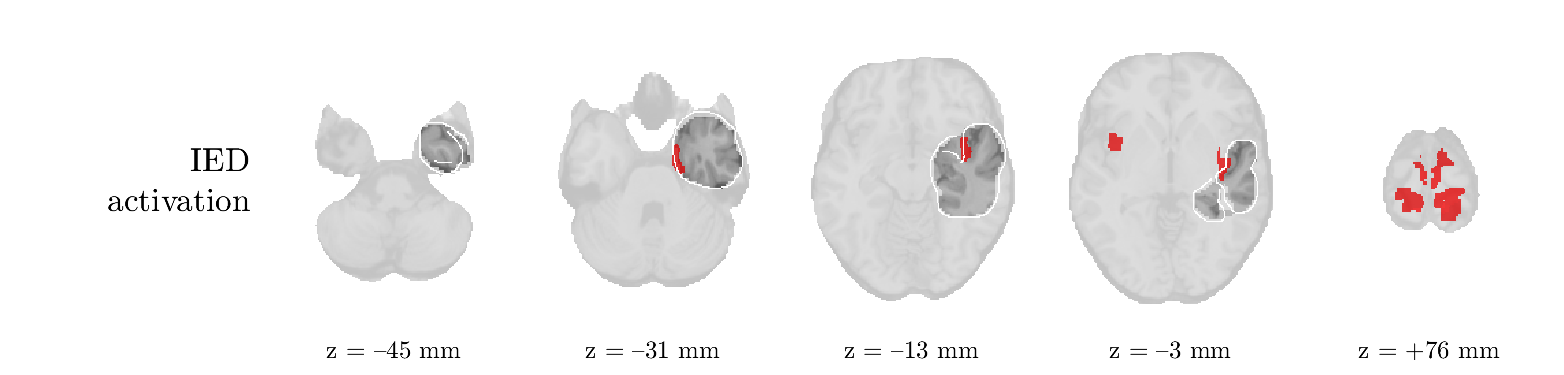

We analyze the solution with sources. Figure 1 shows the EEG signatures and HRF waveforms. One of the sources is highly correlated to the MWF reference (in grey), which was already known from Table B.3. This IED-related source had a typical low-frequency spectrum, which is expected for the typical spike-and-wave interictal discharges. The topography is relatively diffuse, although the highest amplitudes are mostly in the left hemisphere. This is in accordance with the lateralization of ictal onset zone (left temporal lobe, cfr. Table 1). There are some noteworthy observations to be made about some of the other components. The fourth has an unusually sharp spectrum, is mainly localized on two nonadjacent center electrodes, and is sustained for a single period of many seconds Hence, this component likely captured an artifact (of yet unknown origin), although we spotted no large-amplitude changes in the EEG itself. Similarly, the third source is only present at one frontal electrode, and exists in a frequency range above 20 Hz. It might represent a muscle artifact, e.g., due to frowning or twitching of some muscles in the forehead. The HRFs of all ROIs are shown in Figure 1(b). Two of the basis functions seem to have converged to a very similar waveform, which is an unfortunate possibility if two initial HRFs are too close to the same local optimum in their respective parameters. This reduces the expressive power of the basis set, which is clearly visible, since many ROIs have a nearly identical HRF. One of the twenty ROIs with the highest-entropy HRF overlapped the IOZ, although clearly this HRF (bold line) is not among the most dissimilar waveforms for this patient. This is also visible in Figure 2: both the HRF entropy and extremity maps show a small overlap with the delineated IOZ. Despite the good correspondence in the EEG domain, no significant (de)activation of the IED-component is found inside the IOZ.

We analyze the solution with sources, and show the results in Figure 3 and 4. As for patient 1, we found a source which is strongly correlated to the MWF envelope, and which had a mostly low-frequency behavior characteristic for spikes. The topography is mostly uninformative, and does not clearly correspond to the patient’s clinical data. The third source is mostly present at both sides of the head, is very sparsely active in time, and has a high-frequency content: this is most likely an artifact due to the neck muscles. Again, there is one of the highest-entropy HRFs which belongs to a ROI in the IOZ. Now, the waveform is clearly resolved from the other HRFs, through the strong initial dip (before 0 seconds). Such a dip is sometimes observed in HRFs, but its underlying physiological mechanism is not yet fully understood. It is possible that this dip reflects altered vascular autoregulation near the IOZ (cfr. the explanation in the Section 1 of the main text), or a rapid depletion in oxygen due to IED generation (before the IED becomes visible on the EEG). Figure 4 furthermore shows that the IED-related component is significantly active in parts of the IOZ, and deactive in others. As mentioned earlier, this deactivation may or may not be due to errors in sign correction. Interestingly, the ROI with the high alteration in neurovascular coupling is distinct from both the activated and deactivated ROIs.

We analyzed the solution with sources, and show the results in Figure 5 and 6. There is one source which is mostly correlated to the reference (but not extremely, see also Table B.3). This source had a right-temporal focus, conform the diagnosis in Table 1. The second source illustrates the phenomenon of an erroneous sign exchange between the spatial and spectral profiles. Also one of the HRFs has a negative polarity, which is a failure of the sign correction procedure (in this case, because there is exceptionally no positive overshoot). However, the HRF variability metrics are still interpretable, and indeed two ROIs among the ones with the highest-entropy HRFs overlap with the IOZ. The IED component is significantly active in a tiny portion of the IOZ (cfr. Figure 6). The second source is significantly active in symmetrical parts of the parietal lobe. Given its ongoing fluctuation over time, we hypothesize that this source captures a resting state network (RSN).

We analyze the solution with sources, and show the results in Figure 7 and 8. There is a clear IED-related component, with a very high correlation to the MWF reference, a typical spectrum, and an anterior-temporal focus, which corresponds very well to the patient’s diagnosis (cfr. Table 1). The fifth source seems present at only one channel, and has spectral harmonic at Hz and Hz. One of these peaks is reminiscent of the fourth component in patient 1. As Figure 8 shows, the HRF entropy and extremity prove to be strong biomarkers for the IOZ in this case, and also the significant IED activation and deactivation allow correct localization. In Figure 7, it is clear that some HRFs may still have the wrong sign, which means that the interpretation of ‘active’ and ‘deactivated’ is flipped in those ROIs. Hence, regions of significant deactivation are in fact significantly activated. The fourth source had a significant overlap with the auditory RSN, and its spectrum reveals activity in the band.

We analyze the solution with sources, and show the results in Figure 9 and 10. One source is strongly correlated to the MWF, while the other source is likely an artifact, given its very sparse temporal profile. Both sources coincide at one high-amplitude peak, by which we infer that this is probably an artifactual period in the signal. Indeed, when inspecting the original EEG signals, we found high-frequency muscle artifacts at these times. This source also had no significant activation in its spatial map, which corroborates its non-neuronal origin. The IED-related source had a broader spectrum than most other cases, and an uninformative topography. None of the ROIs with high-entropy HRFs is located in the IOZ. The pseudo t-map provides correct localization of the IOZ, however.

We analyze the solution with sources, and show the results in Figure 11 and 12. We found a clear IED-related component, with a characteristic spectrum and a topography which is backed up by the patient’s diagnosis (left anterior-temporal IOZ). The fourth source has a very similar topography and spectrum to the fifth source in patient 5. One HRF inside the IOZ had a high-entropy, and is distinguishable from the others by its very sluggish waveform, i.e., it is smeared out in time, with no sharp over- or undershoot. Also the pseudo t-map provided an accurate localization of the IOZ. Notably, in this patient, the extremity metric misses the deviating HRF in the IOZ (while the entropy metric picks it up). The second source overlapped with the frontal part of the default mode network (DMN), and is active in the and low bands.

We analyze the solution with sources, and show the results in Figure 13 and 14. We found two components which had correlated time courses. At the time of the peaks, we found higher-amplitude events in the EEG with dubious origin, hence they may or may not be artifacts. One of both components is more strongly correlated to the MWF, and its activation is concordant with the IOZ. The second component shows high overlap with the sensorimotor network. For this patient, none of the IOZ’s ROIs had extreme values of either HRF metric.

We analyze the solution with sources, and show the results in Figure 15 and 16. In this patient, there is only a moderate correlation of a component with the MWF reference time course. This component’s topography (left occipital) agrees with the clinical description, however. The HRF extremity (and not the entropy) is high in a small part of the IOZ. Both the significant IED activation and deactivation allow correct localization as well. The second source seemingly captured high-frequency oscillatory activity in the sensorimotor network, similar to the previous patient.

We analyze the solution with sources, and show the results in Figure 17 and 18. The IED-related source had a high correlation with the MWF reference, but an odd bimodal spectrum. Its EEG topography is very consistent with the clinical description. Both HRF extremity and entropy are useful biomarkers for the IOZ. The IED activation and deactivation maps each had a very small overlap with the IOZ. The second source is temporally sparse and captures high-frequency EEG variations, which we identified as muscle artifacts.

We analyze the solution with sources, and show the results in Figure 19 and 20. Again we observe an IED-related source and a seemingly artifactual source with a spectral peak near 34 Hz. Many of the high-entropy HRFs are highly noncausal, and are associated to ROIs inside the IOZ. Hence, with both HRF metrics, the highest-scoring ROIs provides good localization of the HRF. While there are no significantly active ROIs in the IOZ, there are several significantly deactivated ROIs, which may indicate that the sign standardization was not done flawlessly (cfr. also some of the negative-peaking HRFs for patient 10). Surprisingly, the second source had one significantly active ROI, which overlaps with the IOZ, but which did not match its EEG topography. Hence, the nature of this source remains ambiguous.